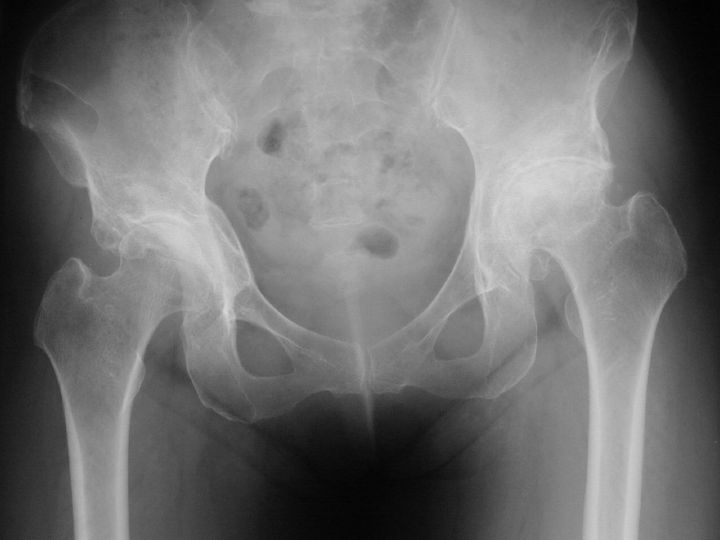

変形性股関節症写真  このレントゲン写真は変形性股関節症で左の股関節が上に上がっています。

赤ちゃんの時に先天性股関節脱臼があり、大人になってから変形性股関節症になり脚長差が生じている人が最も多く見られます。近年はほとんど発生していませんが、過去のポリオの後遺症として下肢が短くなっている事もあります。老人に多い股関節の大腿骨頸部骨折に対して、人工骨頭置換術やスクリューによる骨接合術の手術を行った後にも脚長差が生じる事が多くあります。交通事故などによる大腿骨の骨折による例も時々みられます。